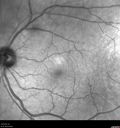

Left eye of patient with valsalva retinopathy in the right eye. Normal Examples Color, FA, OCT